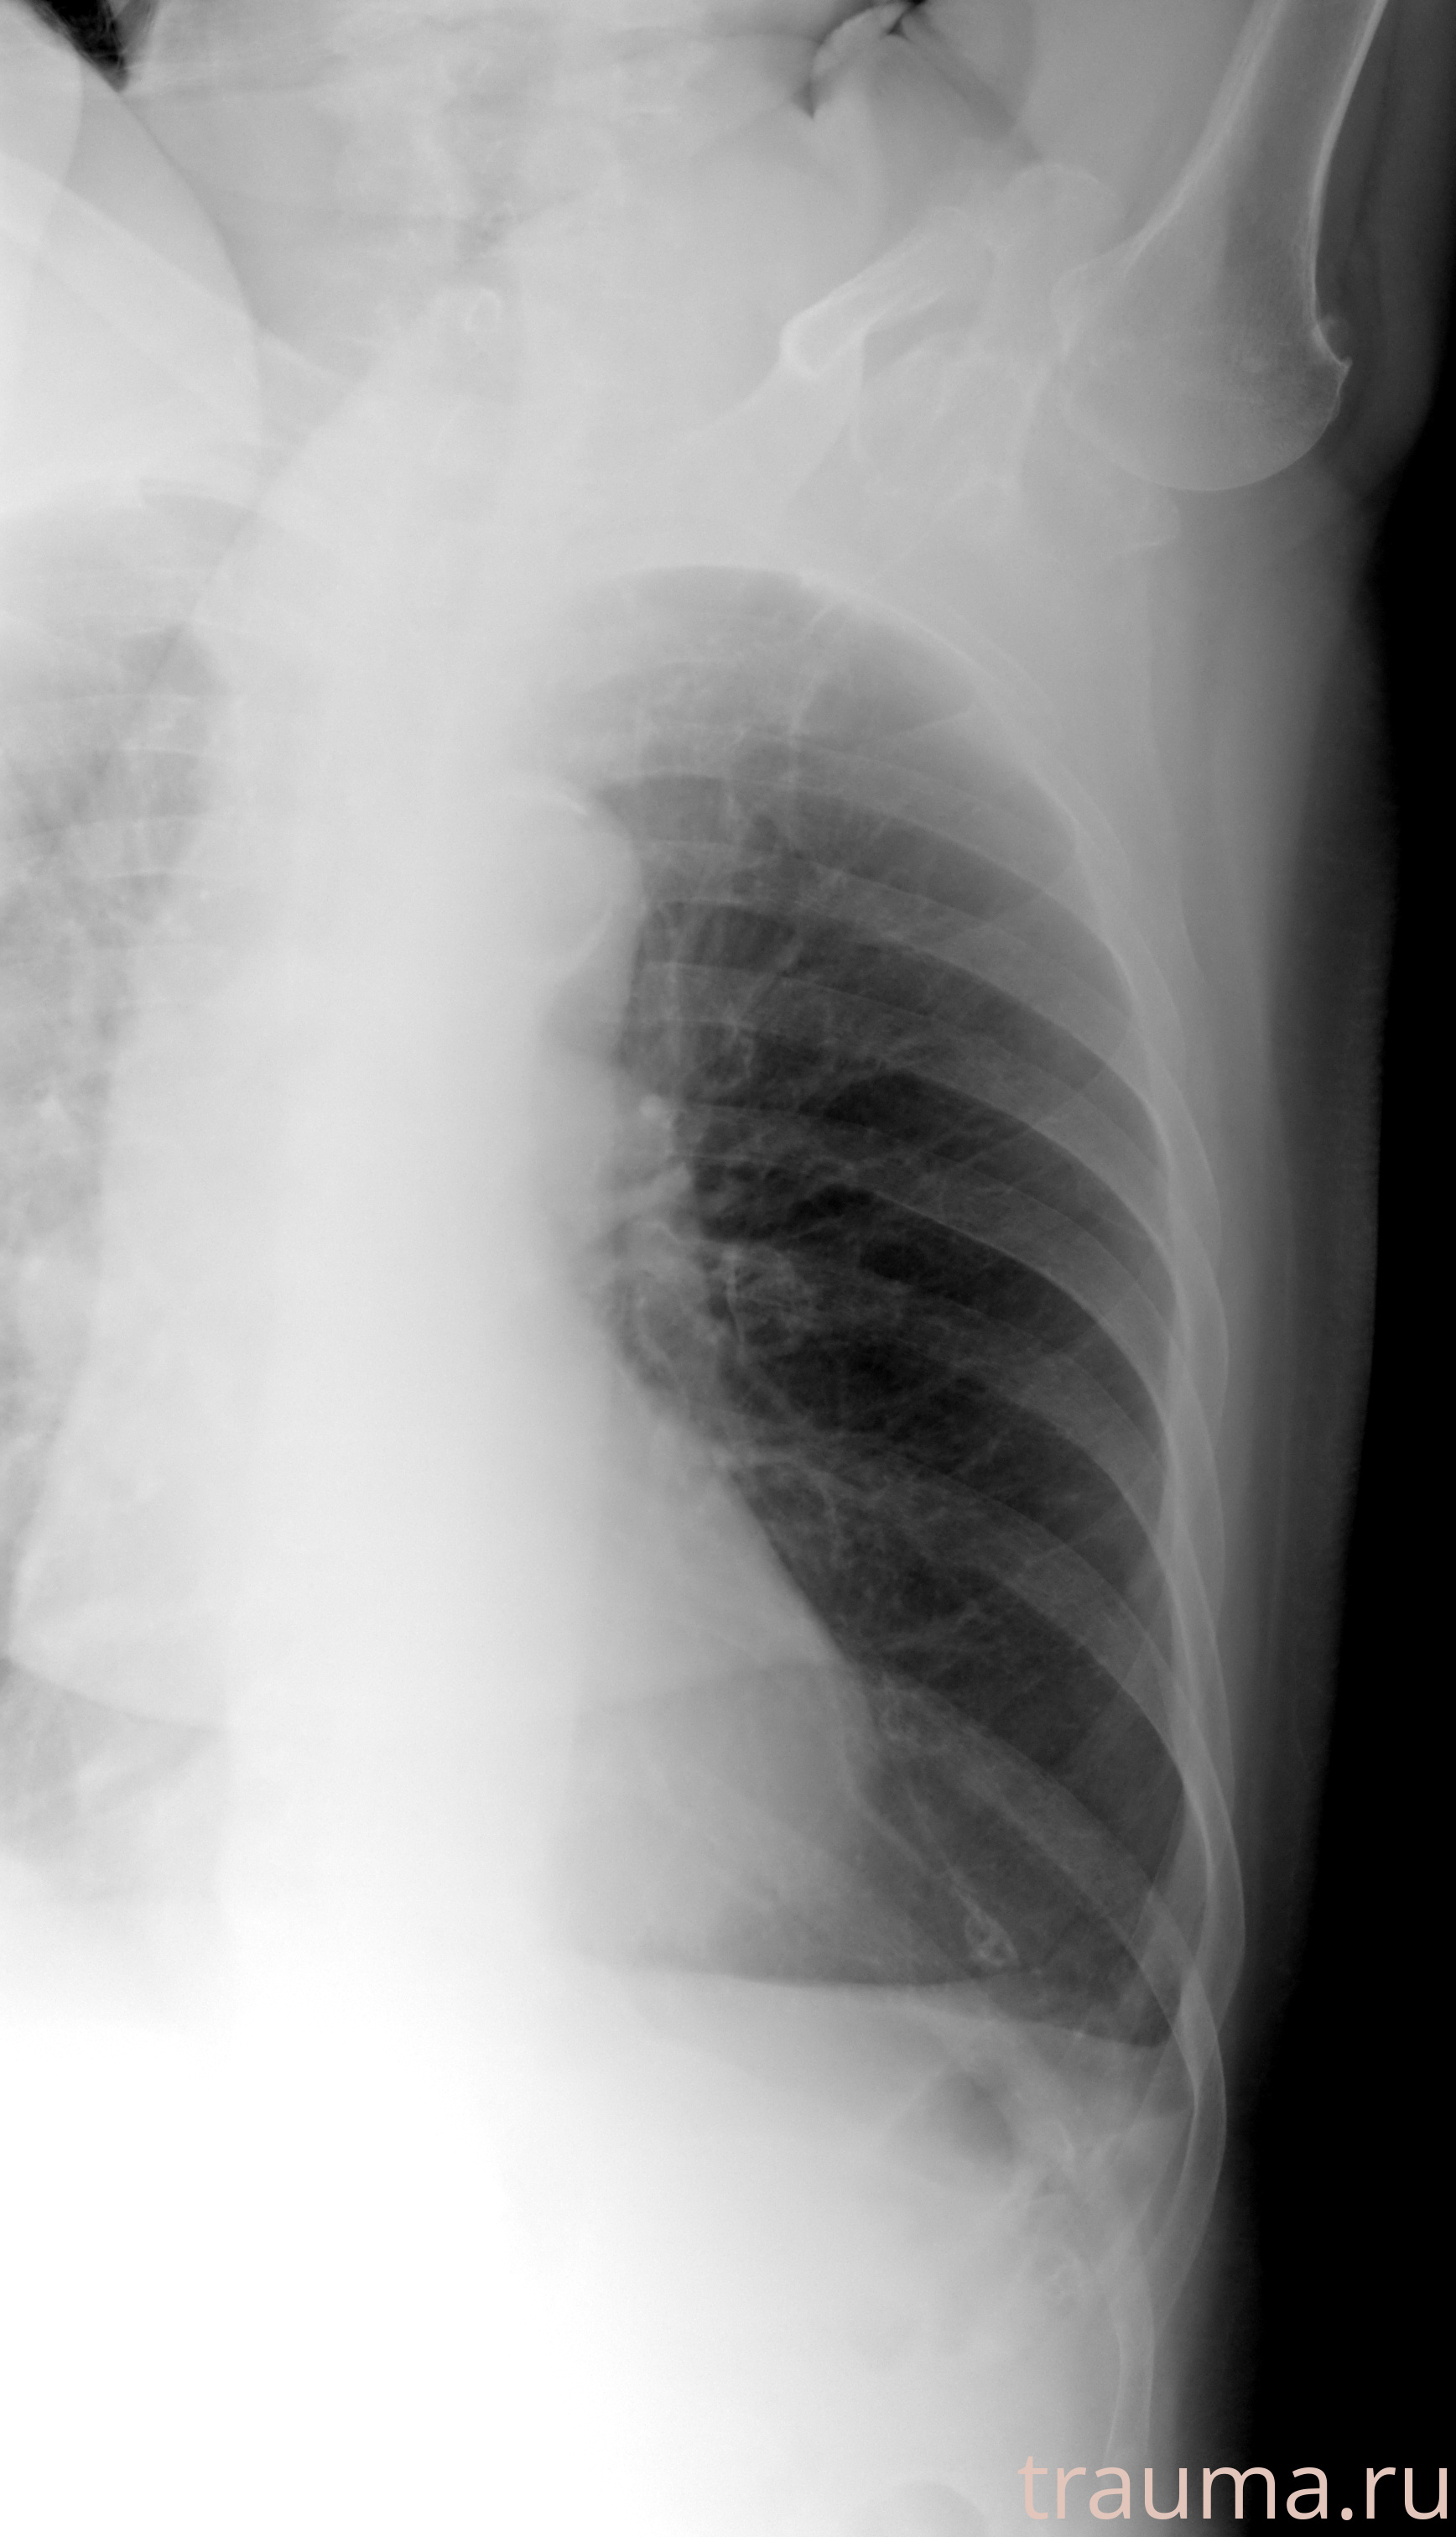

Рентгенограммы

Рентген на дому: по вашему адресу приезжает врач-рентгенолог, травматолог-ортопед с мобильным рентгеновским аппаратом, проводит диагностику травмы или заболевания, делает необходимые рентгенограммы, дает рекомендации по дальнейшему лечению. Получить качественные снимки в домашних условиях возможно благодаря уникальной методике, разработанной МосРентген Центром для института  Склифосовского

Яркость: 1   Контраст: 1   Инвертировать: 0 Увеличение: 1

Перетаскивайте мышь вверх/вниз для контраста, влево/право для яркости. Прокрутка колесом изменяет масштаб. Нажмите Сбросить для возврата к исходному изображению. При увеличении держите мышь в той области, которую хотите рассмотреть.